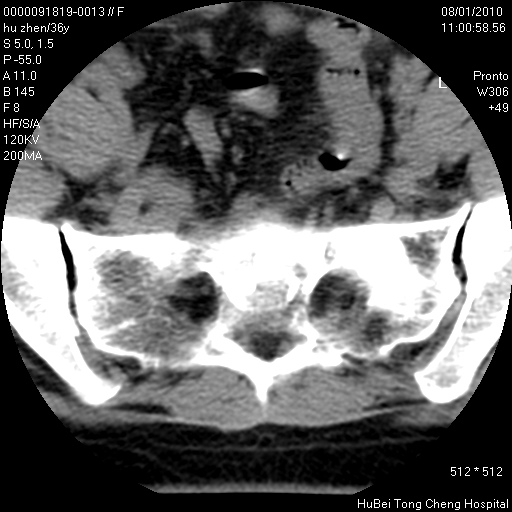

患者 女,36岁。右侧腰腿痛半月余。腰骶椎mr平扫偶然发现骶椎异常信号。

临床诊断:1)腰椎间盘突出症。2)骶椎肿瘤性病变?

骶椎ct平扫(层厚、层距均为5mm),图像如下: